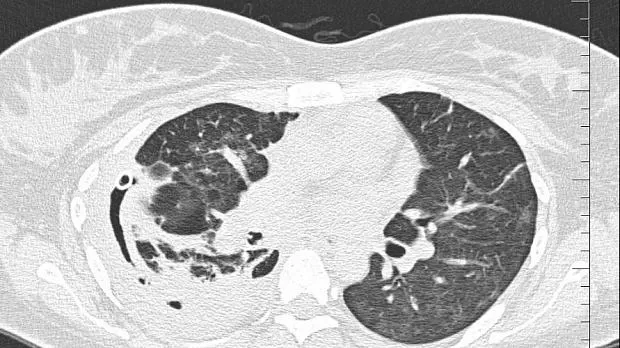

08.06.2020 проведена повторная установка блокатора в промежуточный бронх (блокатор Medlung №13) с хорошим клиническим эффектом (сброс воздуха по плевральному дренажу прекратился через 8 часов после вмешательства). Подтверждено данными Р-КТ органов грудной клетки.